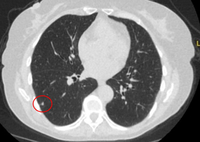

Computed tomography (CT) showing two areas (red circles) of mucoid impaction of the left upper lobe subsegmental bronchi, resulting in appearance that mimics a nodule

From the collection of Dr George Tsaknis, MD, PhD, FRCP(London), MRQA, MAcadMEd, PGCert; used with permission